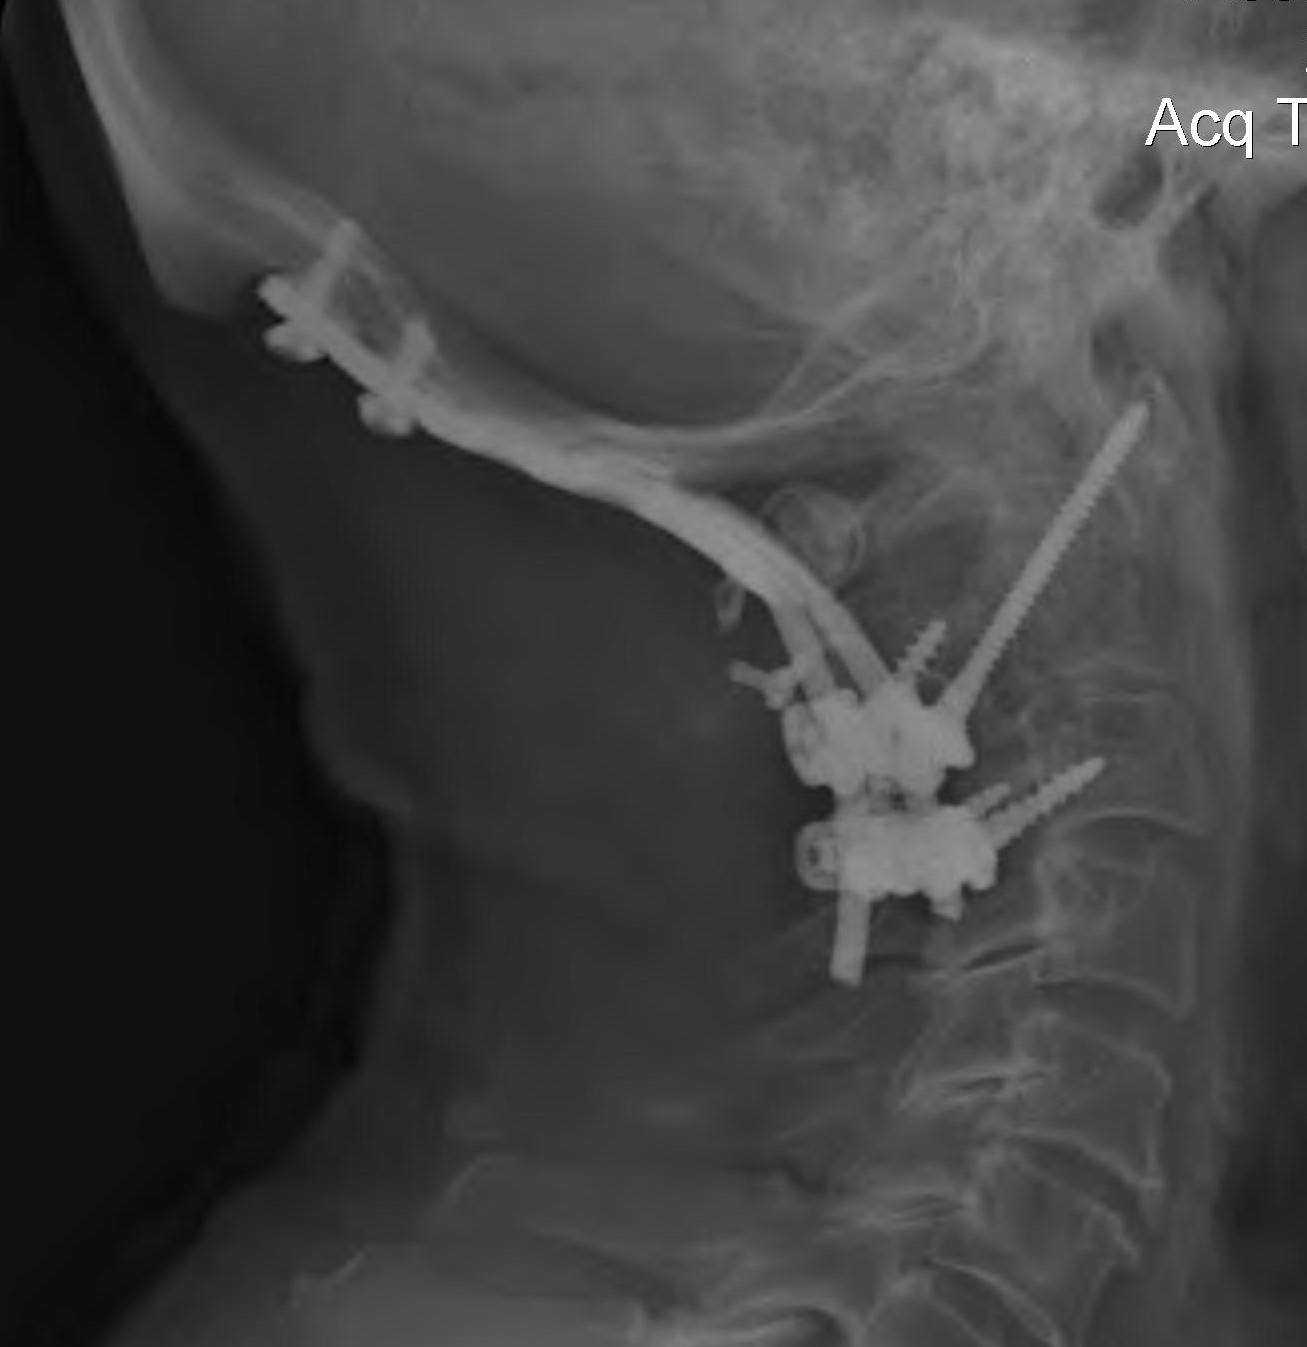

Occipito-cervical fusion

Basilar invagination / Vertical subluxation

Management

Algorithm

1. No symptoms & no cord compression on MRI - observe

2. Cord compression

- occiput to C2 fusion

- +/- C1 laminectomy

- +/- odontoidectomy